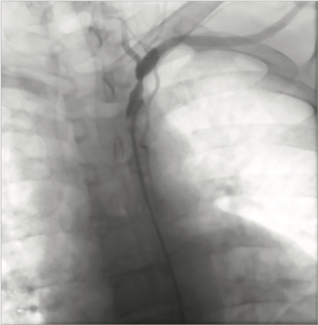

Angiography showed a severe proximal subclavian artery stenosis adjacent to the origin of the left vertebral artery. There was concern that a stent might jail the left vertebral artery.